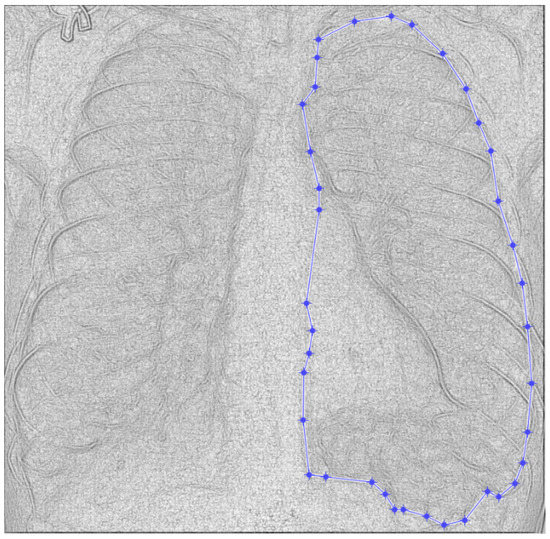

Figure 4. Defining the mask for the left lung of the first patient.

Figure 4 and Figure 5 present the defined masks for the left lung and right lung, framed in blue borders.

Table 1 shows the known fractal indicators, such as the fractal dimension of the CT image of the left lung, d1L = 1.8781 ± 0.3251, and the lacunarity, Λ = 0.0300; and the fractal dimension of the right lung, d1R = 1.8817 ± 0.3267, and the lacunarity, Λ = 0.0301.